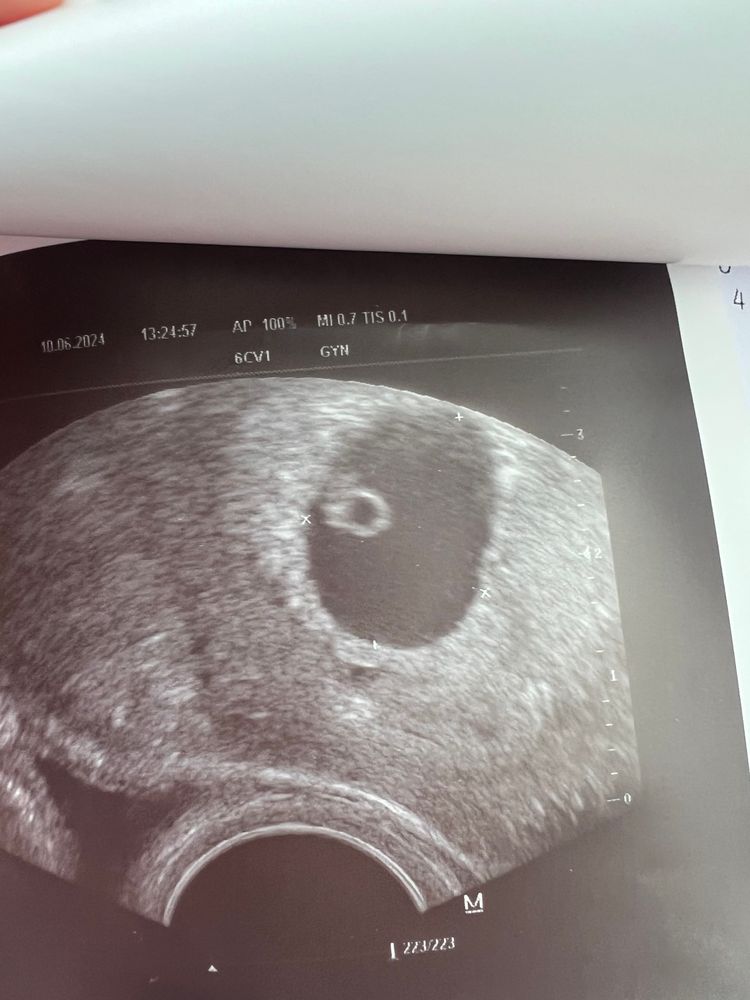

Решилась поставить кружок🥹22 дпп. УЗИ.

УЗИ на 8 недель 5 дней Ре отпустила в добрый путь